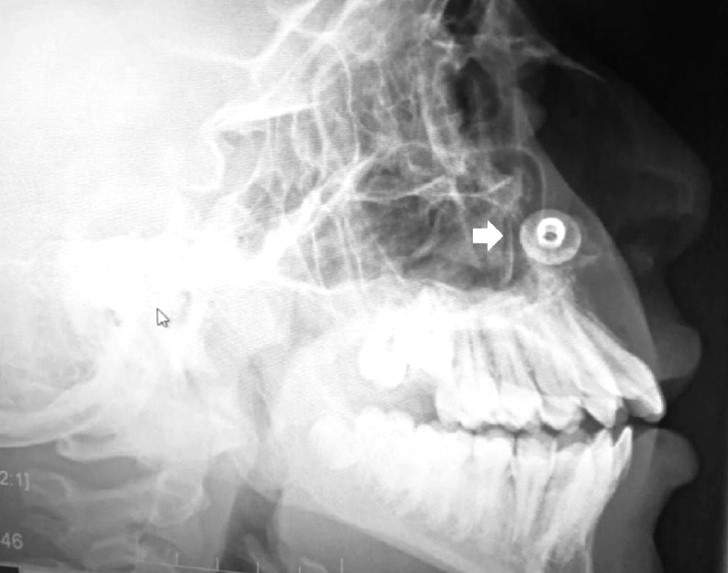

This rare case of symptomless foreign body obstruction became apparent during a routine dental radiography, Need To Know reports.

The teen, 17, denied ever having stuck anything up his nose and had no symptoms of anything being amiss – yet a small metal button was present in the floor of his nasal cavity.

The journal explained: “The object was partially covered with mucus and possibly some crusted material and had a shiny appearance, indicating a metallic nature.

“The surrounding bony structures appeared normal.

“A CBCT confirmed the presence of the foreign body with associated mild inflammation, but no significant bony damage or sinus involvement was observed.